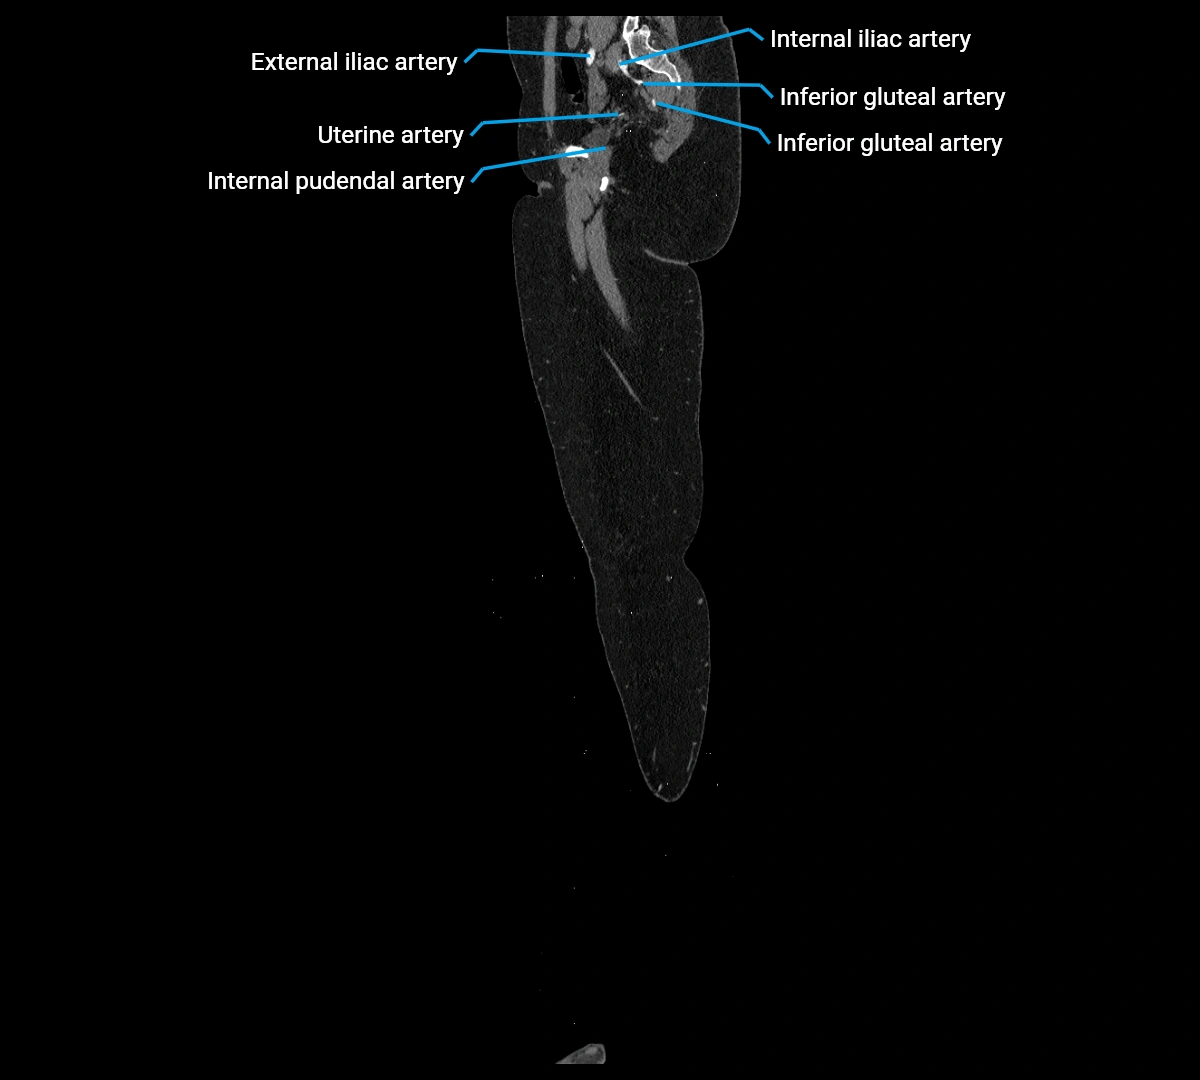

• Paired visceral branches: middle suprarenal arteries, renal arteries, gonadal arteries (testicular or ovarian)

• Terminal branches: right and left common iliac arteries

Contrast-enhanced CT (CTA):

• Gold standard for abdominal aortic imaging

• Provides excellent detail of lumen, wall, aneurysm, thrombus, and branch vessels

• Multiplanar and 3D reconstructions help in aneurysm measurement, stent graft planning, and dissection evaluation